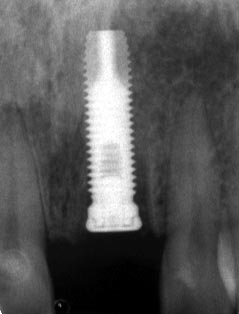

קיימים מספר סוגים של שתלים ביניהם צילינדריים, חרוטיים, מוברגים ובלתי מוברגים. סוג השתל שבו ישתמשו אצל כל מטופל הוא לפי החלטת המשקם והכירורג ותלוי בין השאר במיקום הרצוי של השתל בלסת ובכוחות שיופעלו עליו.

בשלב שני תישלחו לביצוע צילומים מתאימים (פנורמי ובמקרים מסוימים C.T.). הצילומים מאפשרים לרופא לוודא הימצאות עצם באיכות מתאימה לביצוע ההשתלה. הפגישה הבאה תהיה המלצה לתוכנית טיפול, הצעת מחיר ובמידה שתתנו את הסכמתכם קביעת מועד להשתלה.